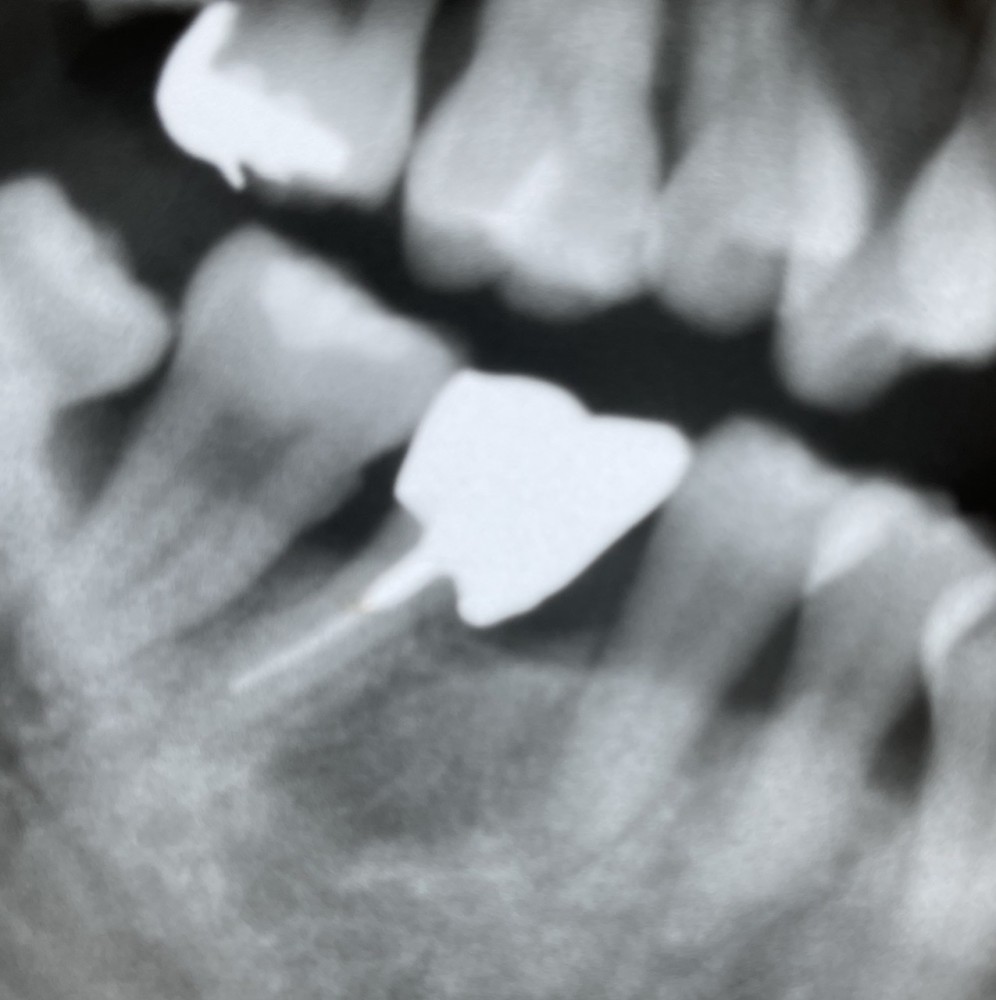

その後、1年経過したエックス線写真がこちらです。

第二小臼歯の遠心に干渉させずにコンタクトポイントをつくるのに工夫が必要でした。

結局、クラウンの近心マージンを意図的にオーバーにすることで近心のコンタクトポイントを作りました。患者さまはセルフケアを大変頑張ってくださっており、プラークコントロールは良好で、歯肉の状態は安定しています。

よく見ても、何が起きているか分かりにくいと思います。